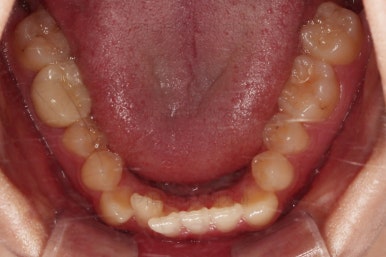

마찬가지로 초진 시 입안의 모습인데요.

위아래 앞니가 삐뚤고, 송곳니는 덧니처럼 불룩 튀어나가 있네요.

위아래 앞니는 안으로 굽어 들어와 있는 옥니(뻐드렁니 반대) 양상이었고요.

그리고 마무리 때 디테일에 문제가 생길 수 있는 부분인데, 윗니 대문니(가장 중간 치아)와 송곳니 사이의 치아를 작은 앞니라고 하는데요.

이 작은 앞니가 가져야 될 크기보다 더 작은 양상이었습니다.

이런 치아를 왜소치라교 표현합니다.